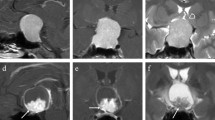

Two hundred forty-six pituitary adenoma patients (84 aggressive, 162 non-aggressive) who underwent preoperative MRI were retrospectively reviewed. The patients were divided into training (n = 193) and testing (n = 53) sets. Clinical information, shape-related, and textural features extracted from the tumor volume on contrast-enhanced T1-weighted images (CE-T1WI), were compared between aggressive and non-aggressive groups. Variables with significant differences were enrolled into Pearson’s correlation analysis to weaken multicollinearity. Logistic regression models based on the selected features were constructed to predict tumor aggressiveness under fivefold cross-validation.

Sixty-five imaging features, including five shape-related and sixty textural features, were extracted from volumetric CE-T1WI. Forty-seven features were significantly different between aggressive and non-aggressive groups (all p values < 0.05). After feature selection, four features (SHAPE_Sphericity, SHAPE_Compacity, DISCRETIZED_Q3, and DISCRETIZED_Kurtosis) were put into logistic regression analysis. Based on the combination of these features and Knosp grade, the model yielded an area under the curve value of 0.935, with a sensitivity of 94.4% and a specificity of 82.9%, to discriminate between aggressive and non-aggressive pituitary adenomas in the testing set.